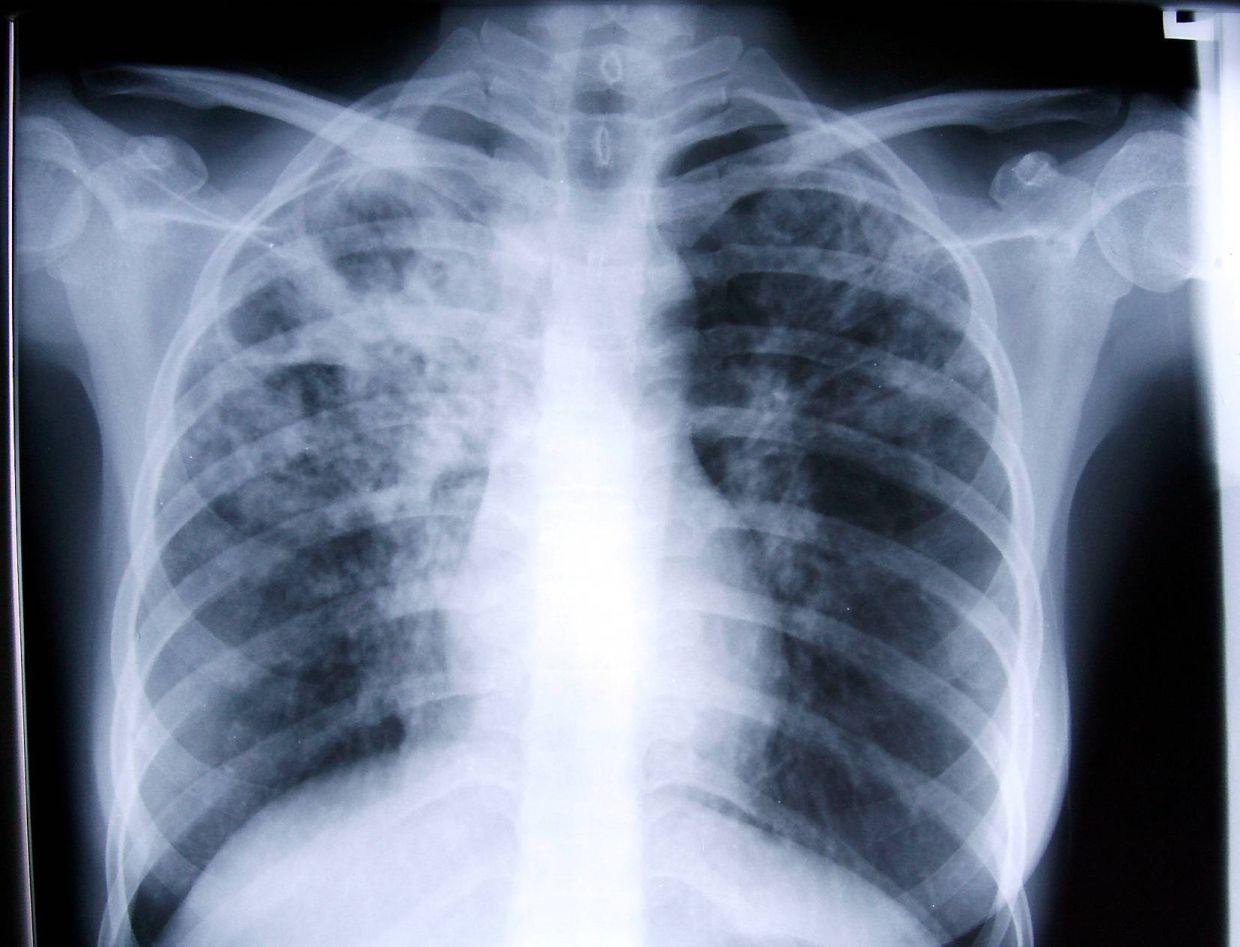

Tuberculosis has come under the spotlight in Malaysia recently, with reports of 10 active TB clusters in the country. In the first six weeks of 2026 alone, 3,161 cases were recorded across all states – a 10% increase from last year.